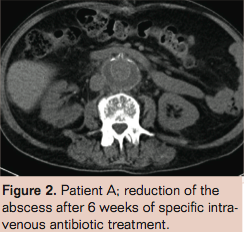

Patient B is a 73-year-old male with a history of subtotal colectomy (because of polyposis coli), transient ischemic attack, type 2 diabetes mellitus, coronary artery bypass grafting, and chronic obstructive pulmonary disease. Because of an asymptomatic juxtarenal aneurysm of the abdominal aorta with a maximum diameter of 7.1 cm, open aneurysm repair was performed with a Dacron tube prosthesis. Two days later he underwent a relaparotomy because of a fascia defect. Recovery was uneventful and he was discharged 2 weeks later. However, 3 days after discharge he returned to the emergency room with abdominal sepsis, a CRP of 238 mg/L and leukocyte count of 20.2 x109/L. Abdominal CT showed an intra-abdominal fluid collection in the right upper quadrant, left lateral, as well as fluid in and directly next to the surgically closed old aneurysm sac (Figure 3). Both the collections in the right upper quadrant, left lateral and next to the old aneurysm sac were drained under CT guidance. Culture revealed a Corynebacterium jeikeium. We presumed that the prosthesis was colonized with the same microorganism. We considered him unfit for definitive surgical treatment because of his severe sepsis and hostile abdomen and therefore started the patient on vancomycin and rifampicin. During his admission, the patient developed several new intra-abdominal abscesses, which were all drained percutaneously.